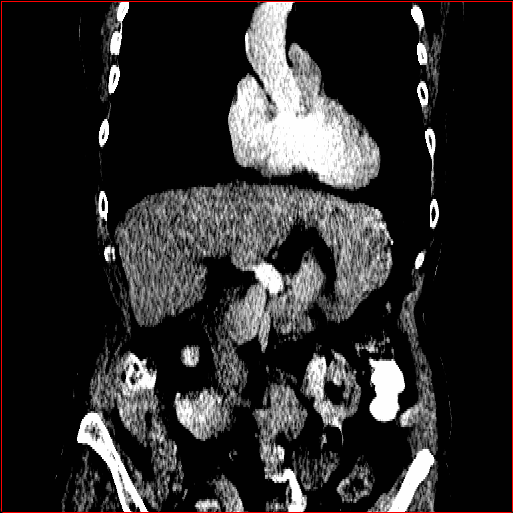

HA-GAN (sun2022hierarchical)

GenerateCT (hamamci2024generatect)

MedSyn (xu2024medsyn)

MAISI-DDPM (guo2025maisi)

MAISI-v2

Figure 2: Qualitative comparison across axial (top row), sagittal (middle row), and coronal (bottom row) views. Columns correspond to different methods. MAISI-DDPM and MAISI-v2 in this figure are unconditional synthesis which do not use ControlNet or segmentation maps.

Qualitative Evaluation:

Figure 2 presents representative slices from the axial, sagittal, and coronal planes. GenerateCT (hamamci2024generatect) is a 2D model, so it lacks inter-slice consistency, leading to poor image quality in the sagittal and coronal views. MedSyn (xu2024medsyn) produces noticeably blurry results with mosaic-like artifacts, such as region inside the red box. HA-GAN (sun2022hierarchical) generates visually sharp images but with mosaic-like artifacts, such as region inside the red box. Also, its voxel spacing is not available, which limits its applicability in real-world medical imaging tasks. Moreover, all three methods are restricted to synthesizing small anatomical regions. In contrast, both MAISI and MAISI-v2 are capable of generating high-quality 3D volumes that span larger body regions while preserving fine anatomical details and realistic structure.